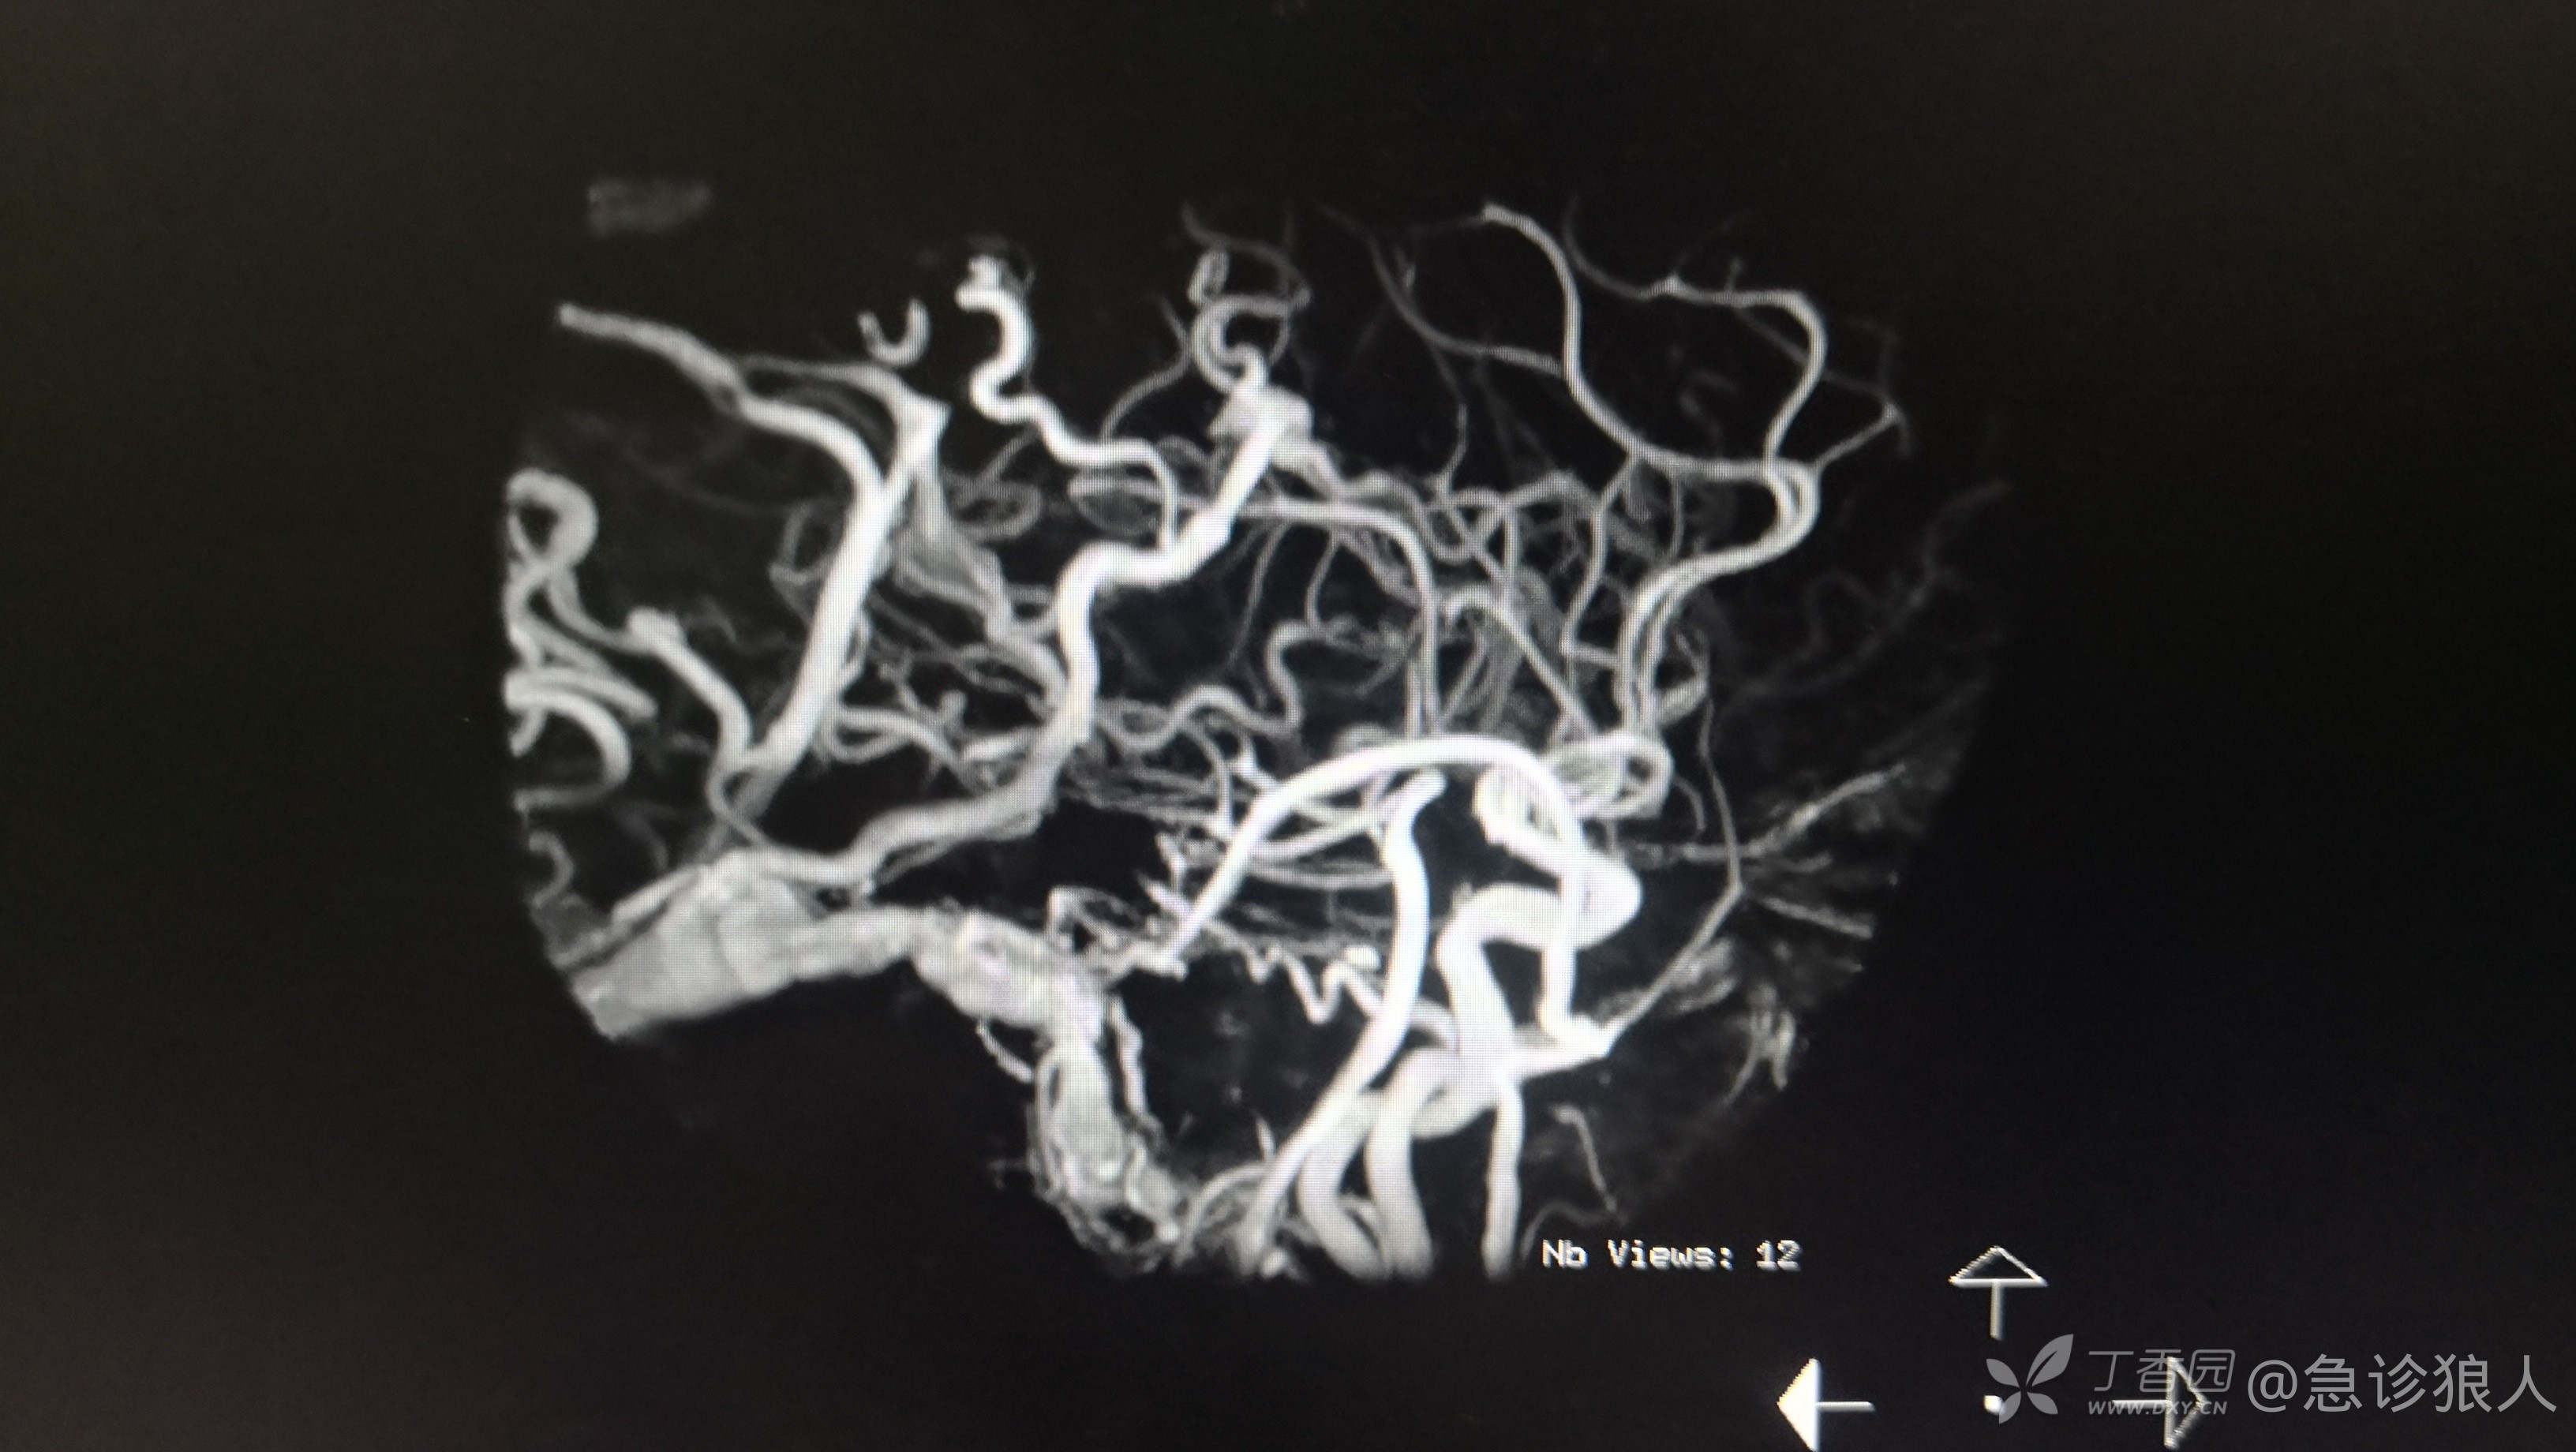

图像如下:

磁共振:1、脑出血(左侧)2、脑血管畸形

这,为啥脑出血CT看不出来,我又反复看了ct确实看不出来。

左侧大脑半球多发杂乱,迂曲血管影,与左侧乙状窦相通,考虑硬脑膜动静脉瘘可能性大。